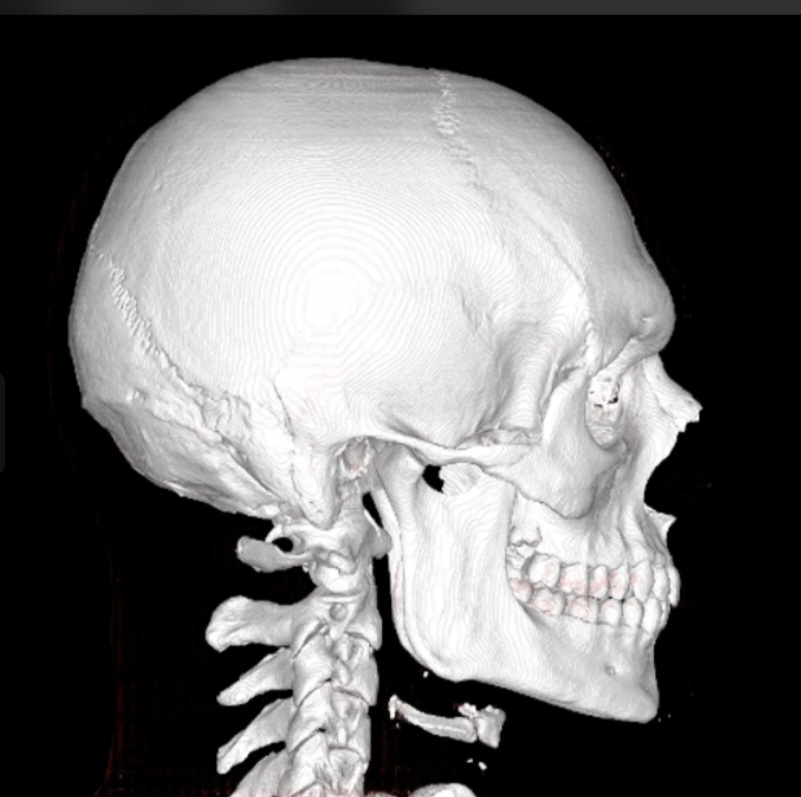

Here are my current CT Scans:

Here are my current CT Scans: